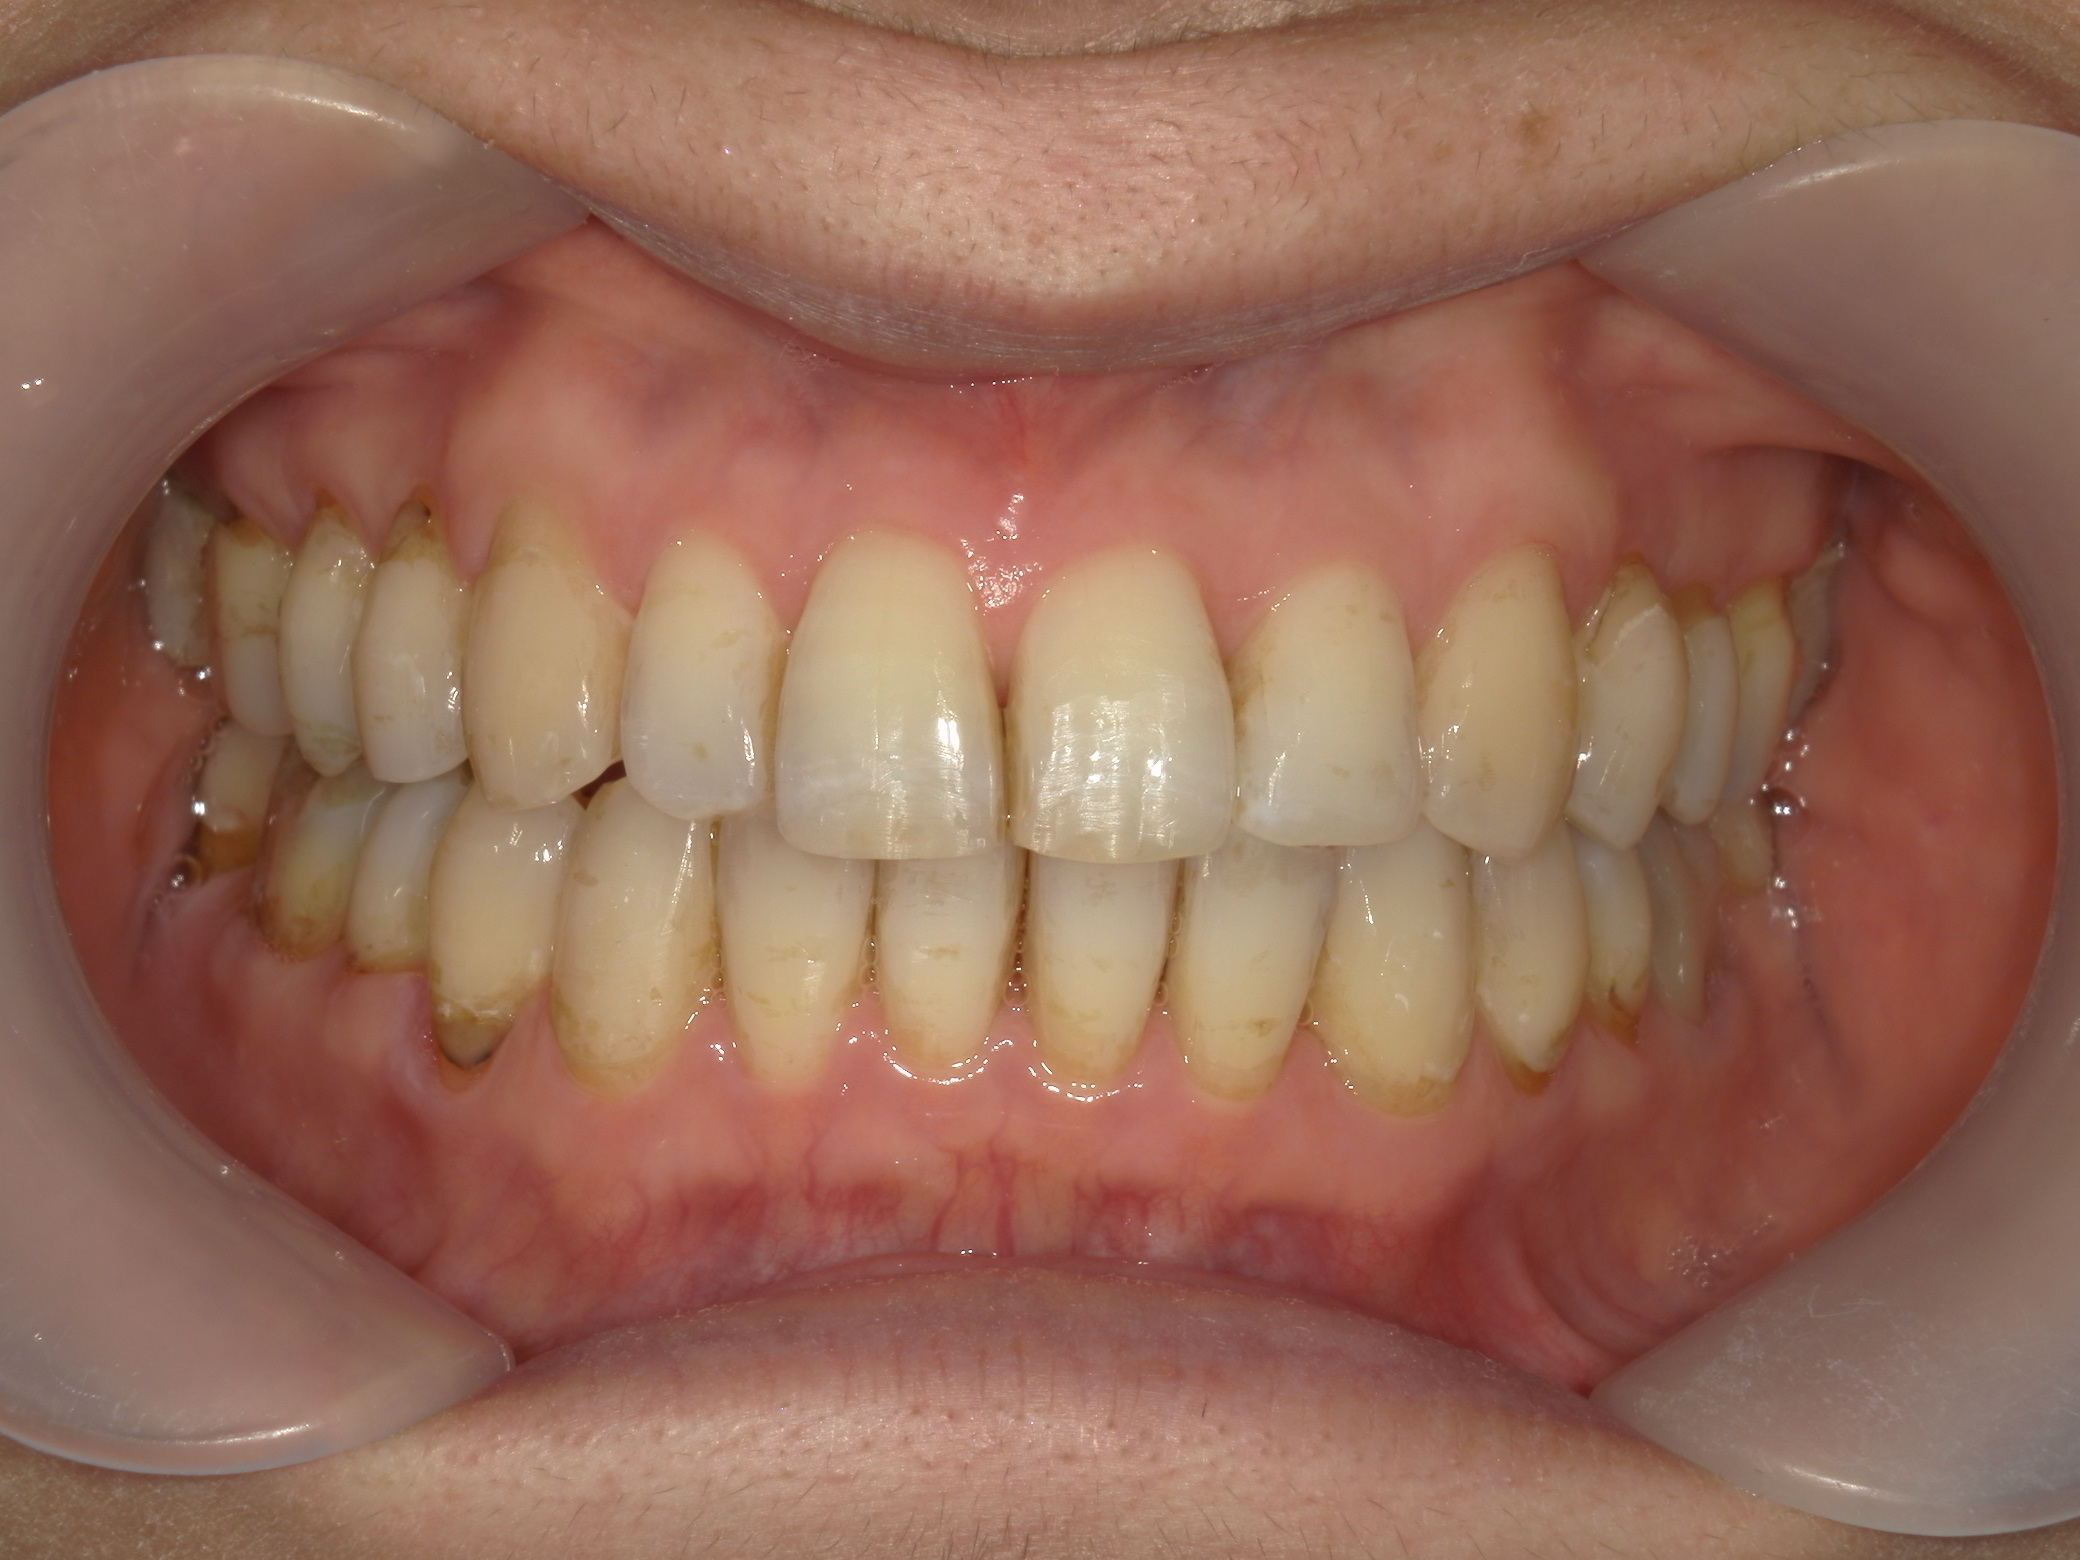

インビザライン矯正 症例(25)

主訴: ㊤前歯が出ていて、噛み合わせが気になる。

| 治療期間 | 1年3ヶ月 |

カテゴリー : ガタガタ(叢生)